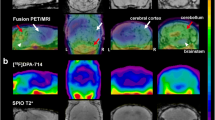

PET imaging of neuroinflammation in the EAE rats

For the severe-relapsing group, uptake of [11C]SMW139 in the spinal cord was significantly higher (37% by comparing the area under the curve (AUC) of the group) at the peak of disease compared to the recovery phase (Fig. 3a). In the severe acute EAE rats, the uptake of [11C]SMW139 in the spinal cord at the peak of the disease was higher compared to the recovery phase (AUC of the group 15% higher), but the difference was lower compared to the severe-relapsing group (Fig. 3d). In the mild acute EAE rats, we did not observe any difference in tracer uptake in the spinal cord between the disease and recovery phase (Fig. 3g) (Additional file 1, Figure 2). In the cerebellum and brain stem, uptake of [11C]SMW139 was also higher at the peak of the EAE compared to the recovery phase for the severe-relapsing (AUC of the group for the cerebellum 18% and brain stem 23% higher) (Fig. 3b, c) and the severe acute EAE (AUC of the group for the cerebellum 12% and brain stem 10% higher) (Fig. 3e, f), but not for the mild EAE group and CFA control (Fig. 3h–l). We also performed static reconstruction for the 5–45 min PET acquisition frame. For the severe-relapsing EAE rats, the uptake of [11C]SMW139 at the peak of the disease was significantly higher compared to the recovery phase in the spinal cord (0.4 ± 0.06 vs 0.3 ± 0.05 %ID/mL, respectively; p < 0.0001), in the cerebellum (0.36 ± 0.07 vs 0.3 ± 0.04 %ID/mL, respectively; p < 0.05), and in the brain stem (0.4 ± 0.07 vs 0.32 ± 0.05 %ID/mL, respectively; p < 0.001) (Fig. 3m). In the severe acute EAE rats, the uptake was also higher at the peak of the disease compared to the recovery phase in the spinal cord (0.38 ± 0.05 vs 0.33 ± 0.05% ID/mL, respectively; p = 0.08), cerebellum (0.37 ± 0.05 vs 0.33 ± 0.06 %ID/mL, respectively; p = 0.17), and brain stem (0.39 ± 0.06 vs 0.35 ± 0.06 %ID/mL, respectively; p = 0.21) (Fig. 3n). There was no significant different between the two scanning time points for the mild EAE rats (Fig. 3o). No significant difference was observed in the CFA control group (Fig. 3p). Representative PET images of sagittal section for the different EAE groups and CFA control at the peak of the disease and the recovery phase is shown in Fig. 4 (Additional file 1, Figures 7 and 9).

Time activity curve (TAC) of [11C]SMW139 uptake in the spinal cord, cerebellum, and brain stem (%ID/mL) at the peak of the EAE disease (red circle) and at the recovery phase (blue square). TAC of [11C]SMW139 in the severe-relapsing (a–c), severe acute (d–f), and mild acute (g–i) EAE animals and CFA control animals (j–l). Quantification of PET imaging in the spinal cord, cerebellum, and brain stem of a single-frame static reconstruction between 5 and 45 min post [11C]SMW139 injection in the severe-relapsing (n = 9) (m), severe acute (n = 6) (n), mild acute (n = 7) (o) EAE, and CFA control (n = 4) (p). S.C. spinal cord, CB cerebellum, B.S. brain stem. (*, p < 0.05; **, p < 0.001; ***, p < 0.0001). Data are expressed as percent injected dose per milliliter (%ID/mL).

PET images of [11C]SMW139 in the EAE rats at the peak of the disease and in the recovery phase. Sagittal PET images extracted from the static reconstruction of the 5–45 min frame and showing [11C]SMW139 uptake in the brain and spinal cord (arrows) of severe-relapsing (a), severe acute (b), mild acute (c) EAE, and CFA control (d). Arrow heads are showing [11C]SMW139 uptake in a brain draining lymph node